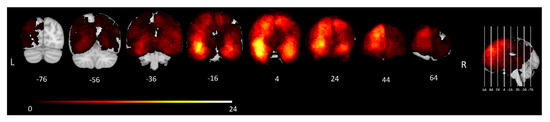

3.1.2. Voxel-Wise Lesion Symptom Mapping